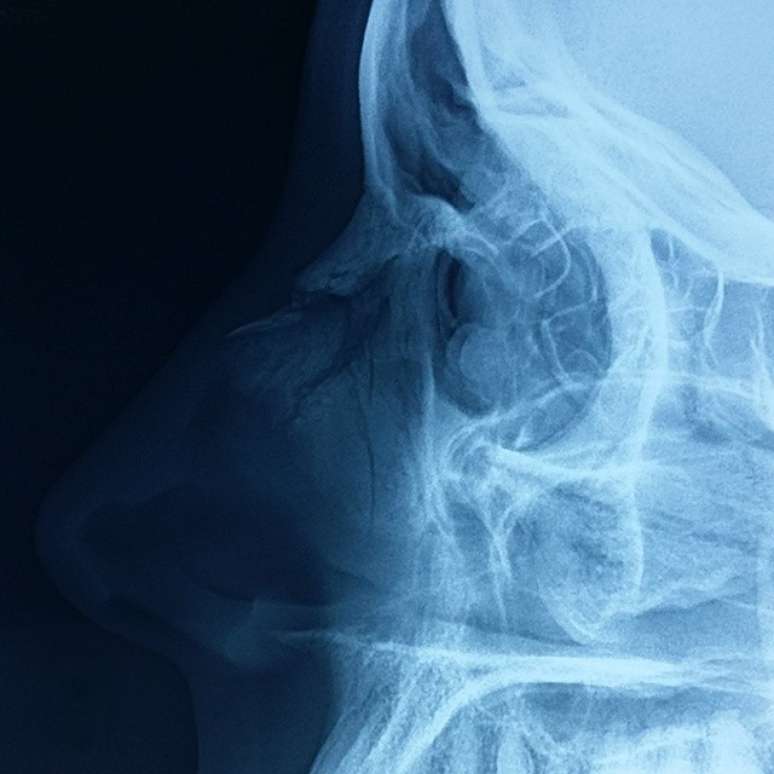

A surfista Maya Gabeira sofreu um novo acidente. Por meio de sua página no Facebook, a brasileira colocou uma imagem de uma radiografia de seu rosto, que diagnosticou um nariz quebrado. A lesão pode resultar em cirurgia na face da bela esportista.

Maya Gabeira postou foto de radiografia em nariz quebrado

A foto colocada por Maya Gabeira mostra claramente o problema no nariz. O acidente é mais um envolvendo a surfista. No fim de 2013, a brasileira caiu ao tentar pegar uma onda gigante em Portugal e chegou a ficar desacordada até ser resgatada no mar. Já há algumas semanas a garota sofreu um corte na perna enquanto surfava.

Veja a imagem postada por Maya Gabeira: